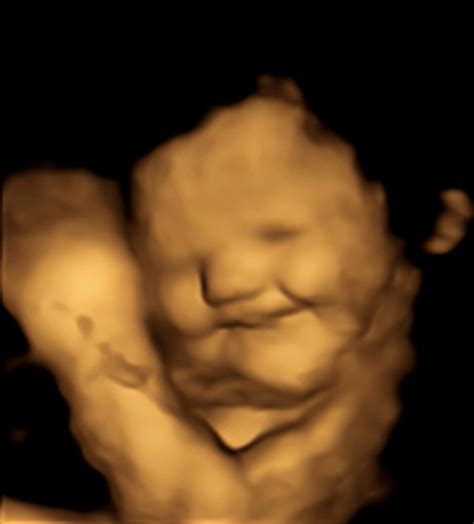

Poleg gibanja, otrok v materinem trebuhu razvija tudi druge sposobnosti. Britanski znanstveniki so z opazovanjem 4D ultrazvočnih slik ugotovili, da se plod v 24. tednu starosti že lahko smeje, pri 36. tednu pa se lahko izraža skozi različne obrazne kretnje, od spusta obrvi do namrščenega noska in širokega nasmeha. Dojenčki v maminem trebuhu pogosto sesajo svoj prst in tudi zehajo.

Vadi mimiko

Dojenček v trebuhu vadi različne izraze na obrazu. Ne gre samo za nasmeh, temveč znak, da možgani skozi živčni sistem pošljejo signale in to pomaga dojenčku, da se razvija.